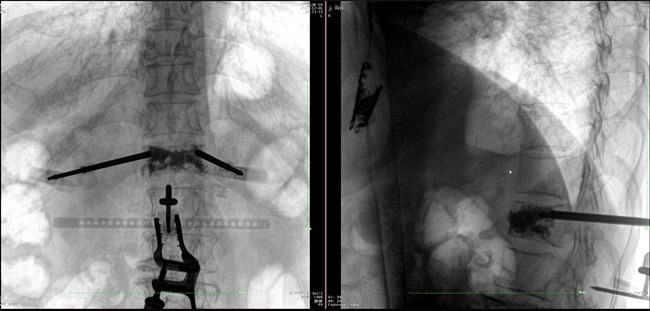

在病人体表切开一个长1-2cm的创口,沿骨科机器人的机械臂定位点方向将克氏针导向套筒,通过创口送至病灶椎体处,并沿套筒方向打入克氏针进行定位。沿导针插入工作套管,取出导针,完成球囊扩张后,通过骨水泥注入器准确地在骨折部位缓慢注入骨水泥,帮助其恢复椎体的形状和强度。

*骨水泥置入效果良好